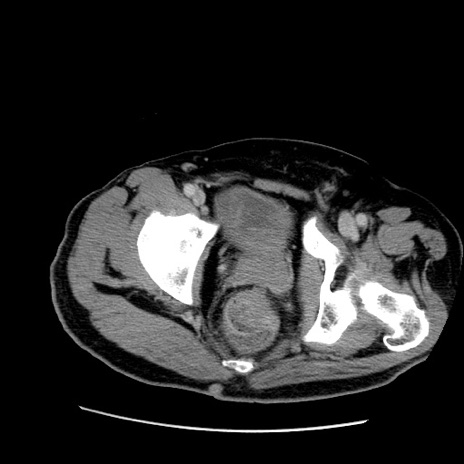

症例22(横断像)

【症例】50歳代男性

【主訴】腹痛

【現病歴】AVMからの被殻出血のため回復期リハ病棟入院中。 本日午後3時頃急に下腹部痛が出現した。

【既往歴】AVM、被殻出血、虫垂炎、高血圧

【身体所見】意識晴明、左半身不全麻痺、会話の理解は良好、36.5°C、腹部:膨隆、全体に板状硬、下腹部正中に圧痛点あり、反跳痛-、筋性防御不明、右下腹部にope scar

【データ】WBC 9400、CRP 0.06